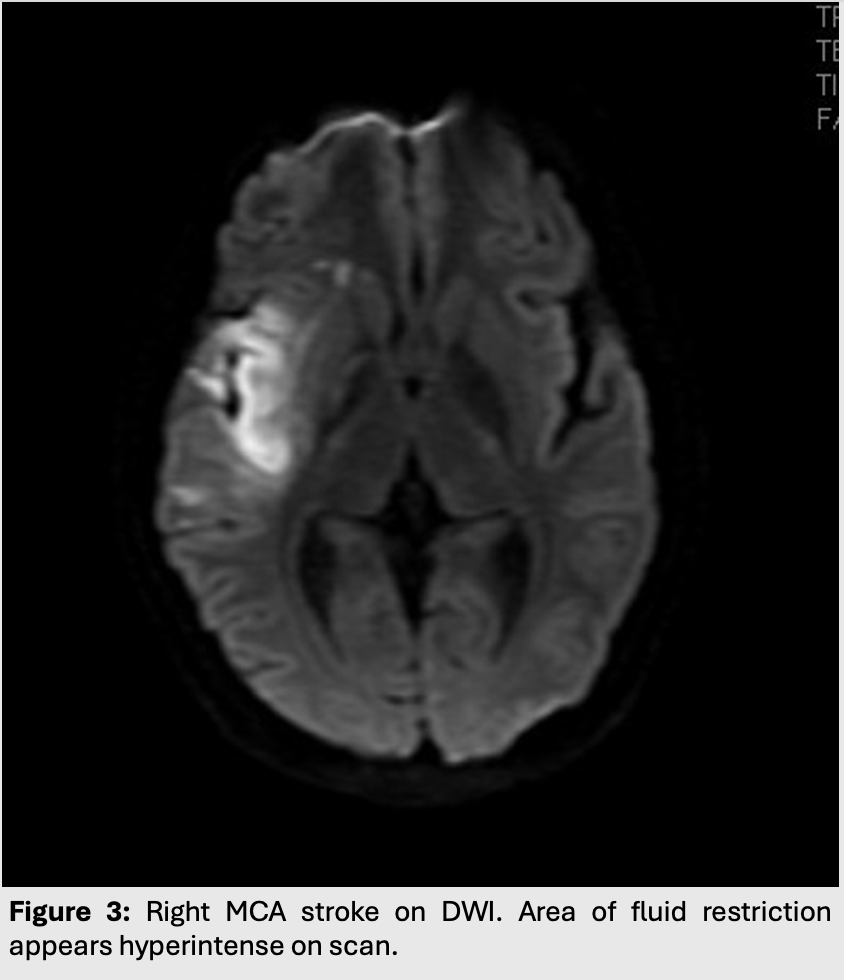

Figure 3: Right MCA stroke on DWI. Area of fluid restriction appears hyperintense on scan.

This leads to edema with restriction of water diffusion. As such, cytotoxic edema will appear hyperintense on both T2/FLAIR and on DWI.

This type of edema is most commonly seen in strokes or ischemic syndromes.